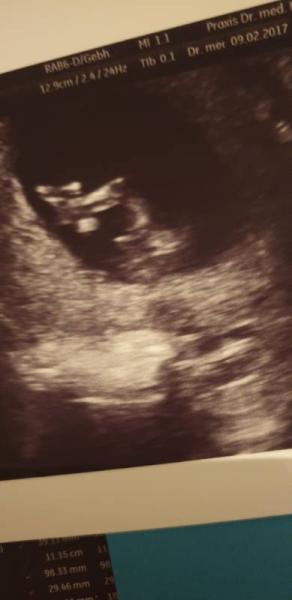

...und das ist ein Bild von der NFM, aber eben im Profil. Bin mir nicht sicher ob da der Nub ist. Auf jeden Fall sah es zwischen den Beinen ganz anders aus beim Schall als beim kleinen.. Ich hoffe so sehr.

Bild zu

Also ich erkenne ein Mädchen Halte dir die Daumen

Also das von deinem "Mädchen/Jungen" find ich sieht neutral aus... könnt mich da ned auf Junge oder Mädchen festlegen Bei deinem jetzigen Bauchzwerg würd ich "eher Mädchen" sagen